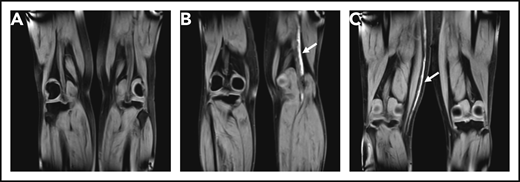

Coronal MRDTI images from 3 study patients. (A) MRDTI negative for DVT with symmetric low signal intensity in both popliteal veins, despite an incompressible popliteal vein in the left leg upon CUS. (B) Asymmetrical high signal intensity in the left popliteal vein diagnostic of acute recurrent DVT of the left leg (arrow). (C) Asymmetrical high signal intensity in the right great saphenous vein diagnostic for acute thrombophlebitis, but not DVT, in the right leg (arrow).

A total of 111 patients (36%) had a MRDTI positive for DVT, of whom 99 were not receiving anticoagulant treatment at the time of inclusion in the study and started anticoagulant treatment (Figure 2). Twelve patients were on anticoagulants at the time of study inclusion, and their treatment was modified after diagnosis. Thus, the overall prevalence of recurrent DVT at baseline, including 111 patients with MRDTI positive for DVT and the above-mentioned 5 patients with recurrent VTE diagnosed otherwise, was 38% (116 of 305). The baseline prevalence of recurrent DVT in patients on anticoagulants at inclusion was 21% (14 of 68; Figure 2). Figure 3 and supplemental Videos 1-6 show examples of MRDTI images and movies of 3 patients in which clear high signal intensities were seen in cases of acute thrombus and symmetrical low signal intensity in the absence of an acute thrombus.